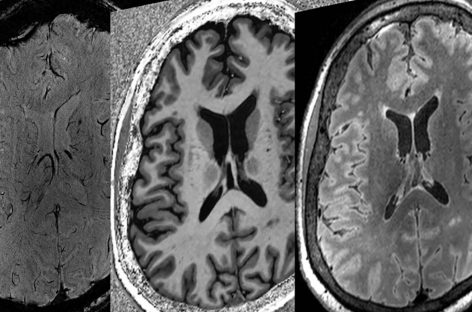

Inteligenţa artificială poate identifica boala Alzheimer cu o precizie ridicată, sugerează noi dateastăzi, 16:40